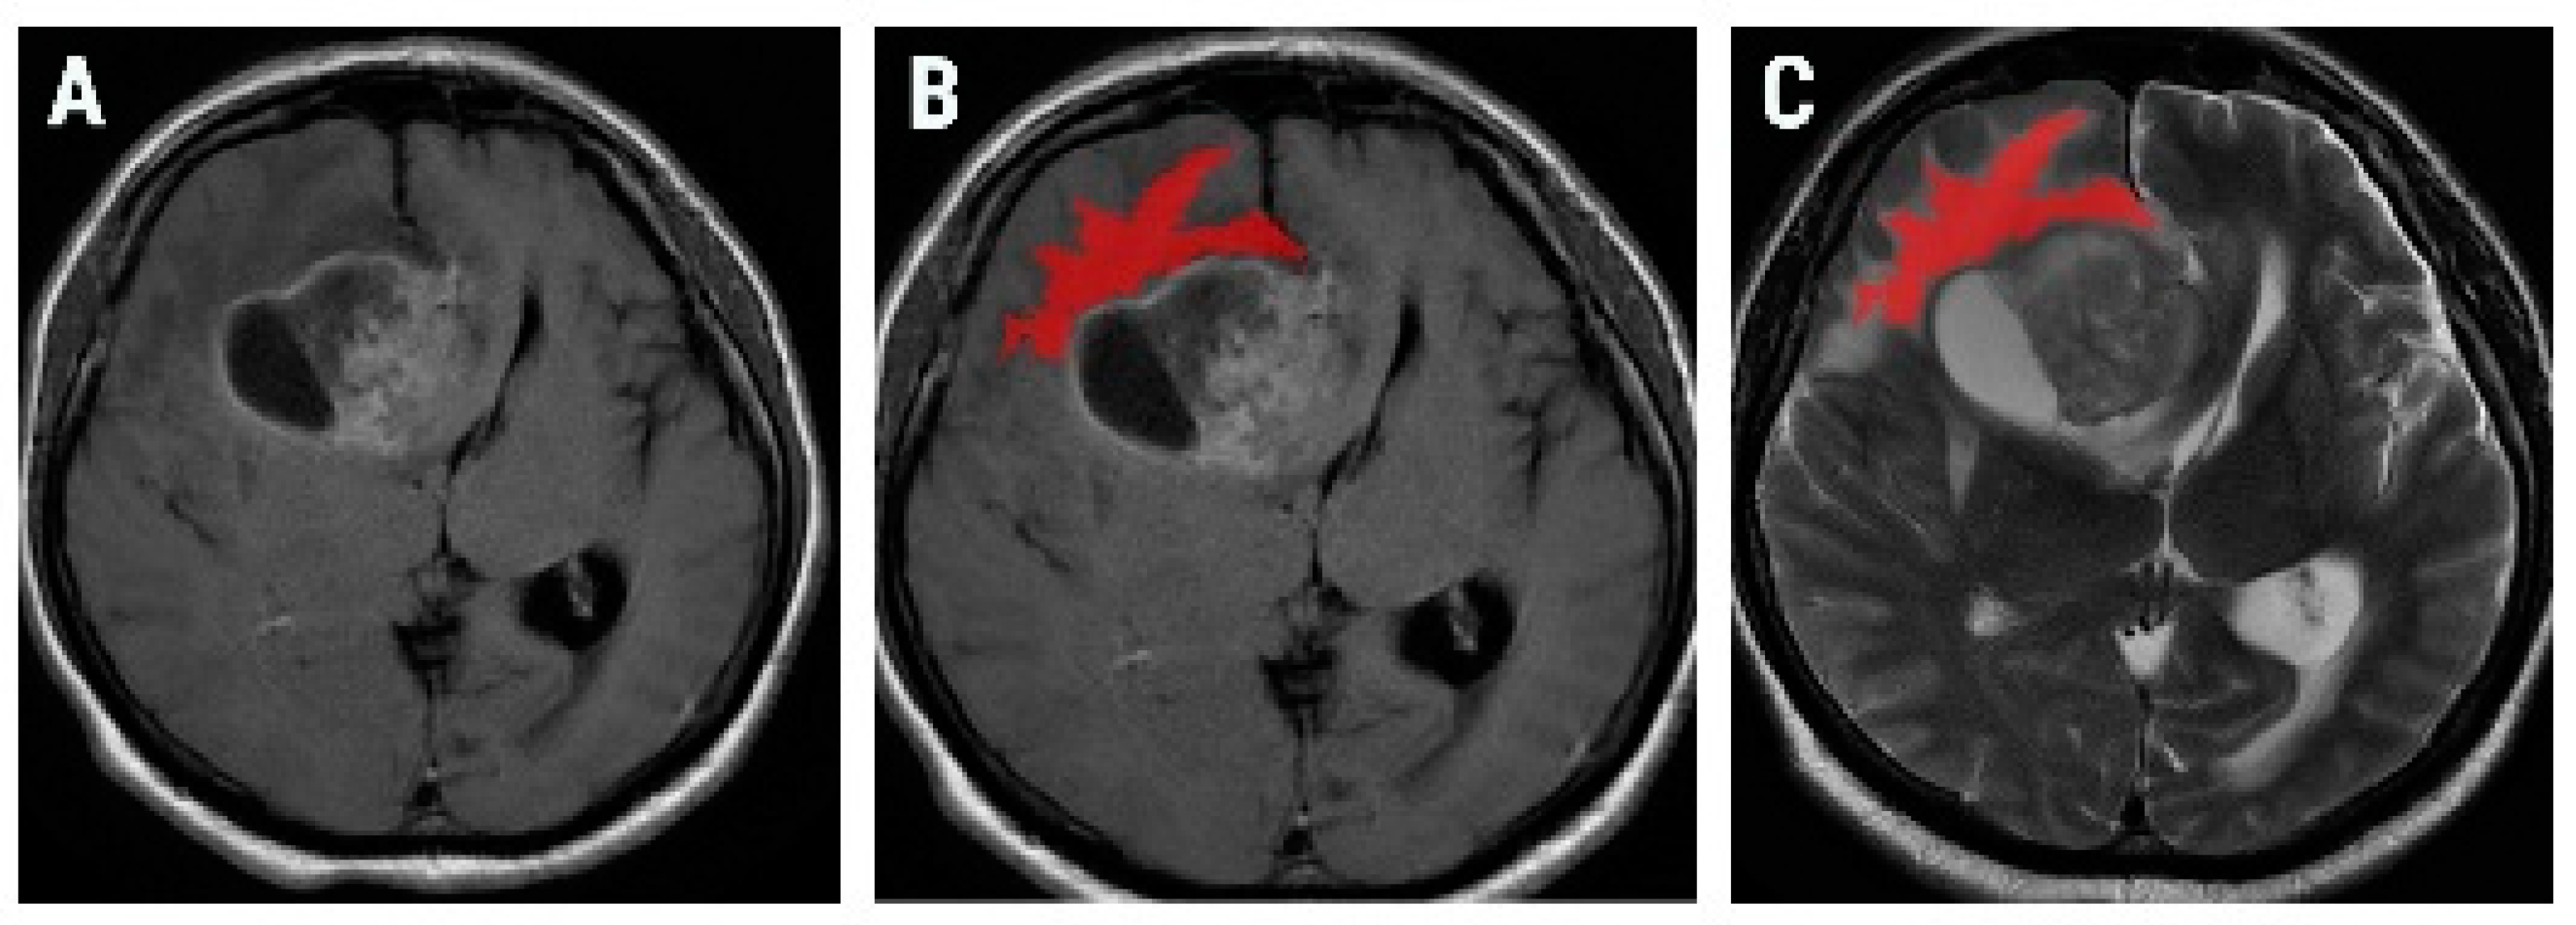

2.3. Texture Analysis Protocol